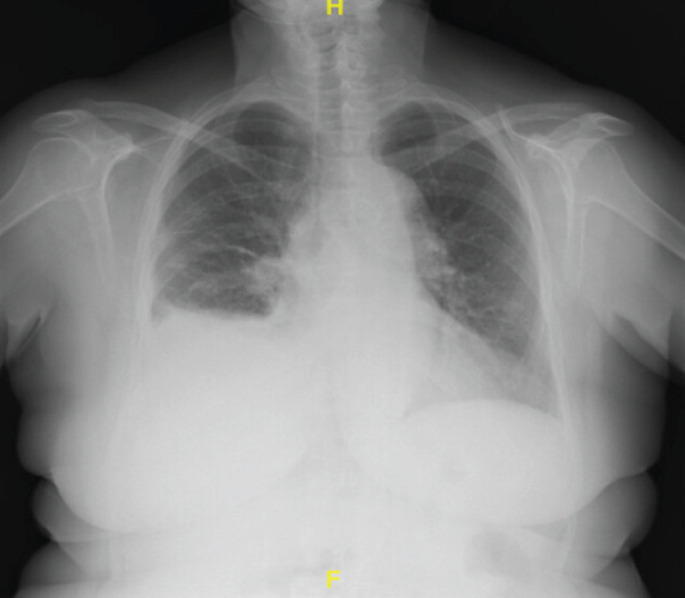

Abstract Image